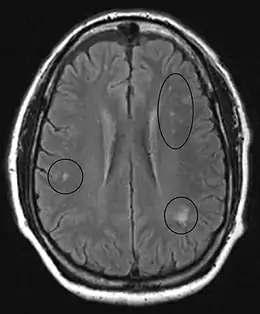

MRI of the brain may show periventricular white matter abnormalities. MRI of the spinal cord may show linear hyperintensity in the posterior portion of the cervical tract of the spinal cord, with selective involvement of the posterior columns.